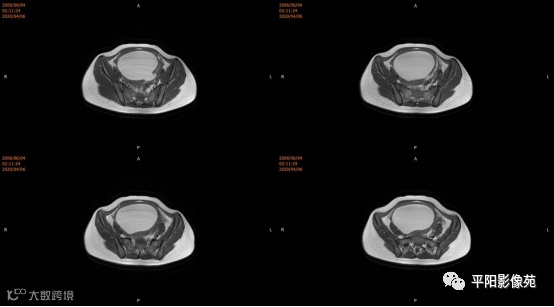

4.MRI检查 对软组织分辨率好,能够清晰区分子宫及阴道,对子宫内膜、结合带、肌层可清晰分辨;能明确子宫、宫颈、阴道结构异常的部位、范围、性质等。宫腔内经血潴留时,宫腔内见短T1长T2信号。